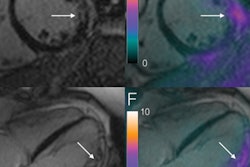

The use of PET/MRI to diagnose and assess a variety of conditions and diseases is expanding. The latest example comes from the U.K., where researchers are using late gadolinium enhancement and FDG uptake as the key indicators to help shed light on suspected cases of cardiac sarcoidosis, particularly for patients who are at greatest risk of death, arrhythmia, and heart failure. Go to the Molecular Imaging Community, or click here.